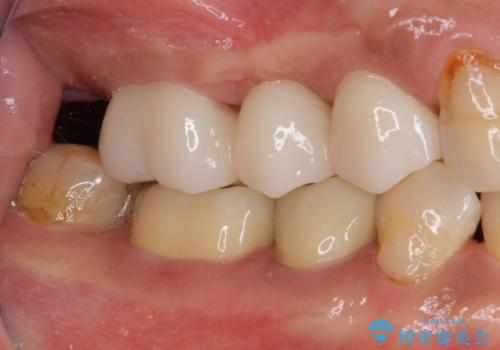

欠けてしまった奥歯 セラミッククラウンによる補綴治療

高強度のジルコニアクラウンとしたことで、強い咬合力でも壊れず、審美性を維持しやすい治療を行うことができました。